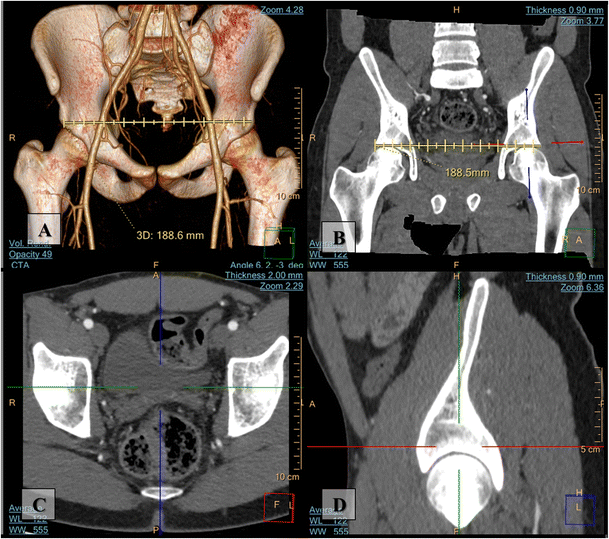

Importance Of Both Internal And External Iliac Artery Interrogation In Pelvic Trauma As Evidenced By Hemorrhage From Bilateral Corona Mortis With Unilateral Aberrant Origin Off The External Iliac Artery